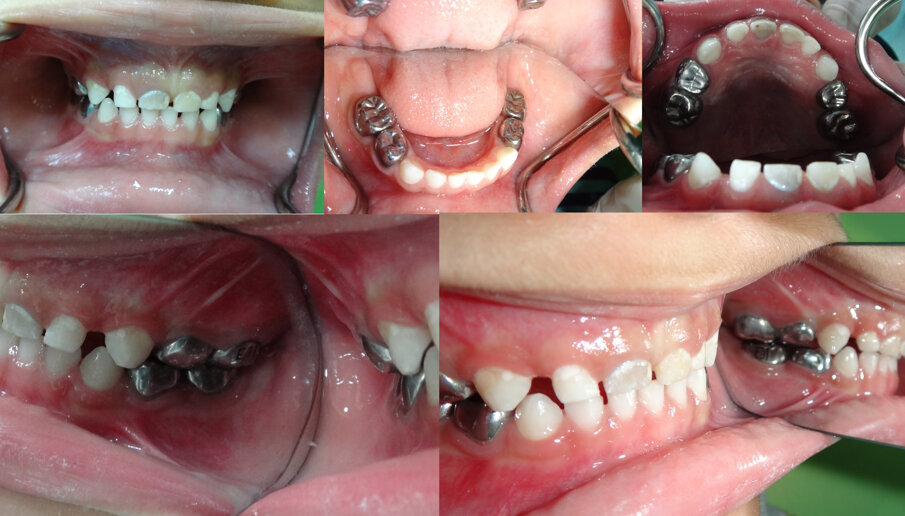

Figures 3 (a, b, c, d & e): Immediate post- treatment completion images. All Es and Ds were restored using the HT. Notice the good gingival status. Using the primary canines as a guide, opening of the bite is noted in Figures 3 (d & e). 51 became discoloured with no sinus present. No known trauma. We opted to manage 51 conservatively as x-ray showed no pathology. The patient by this time had no experience of LA, avoided GA and was gradually becoming cooperative.

Figures 4 (a, b, c, d & e): 9 months post- treatment. The patient had no complaints. The occlusion had equilibrated (note primary canines in Figures 4 b & c and compare to Figure 3 a, d & e). All Es and Ds remained asymptomatic. Good gingival health and oral hygiene were noted. As his cooperation improved plans are in place to monitor 51 with a view to carry out pulp therapy in addition to restoring upper anteriors with composite strip crowns.

The SSCs crowns were placed as per the schedule in Table 2. The patient also had simple restorations placed (with no LA) on his upper anterior primary incisors and canines, using simple excavation and GIC with a view to eventually receiving composite strip crowns. Figures 3 (a, b, c, d & e) show the mouth immediately after completion of treatment. The bite appeared open and was initially raised by approximately 1-1.5 mm.

The patient was followed up three, six and ninth months later. He, nor his parents, had any complaints whatsoever. There were no issues with the occlusion, symptoms or signs of pulpal pathosis or sepsis affecting the molars. The bite had completely recovered. See Figures 4 (a, b, c, d & e). The parents’ satisfaction in reaching a positive outcome, without resorting to the use of GA, was very high. Post op radiographs (Figures 5 a & b) showed satisfactory clown placement and no recurrent caries.

MF accepted the minute occlusal changes after cementation of each HT crown. The occlusion clinically appeared to have re-established itself in a very short time (see Figures 3 and 4 using the primary canines as indices) and this was always checked before proceeding with the next phase.